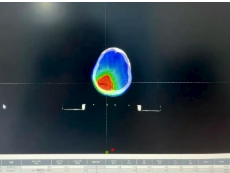

VitalBeam直线加速器落户达州市第三人民医院啦!现已正式投入使用。这个机器可大有来头,它就是在放疗界被誉为“放疗超人”的美国高端进口直线加速器,全市仅此一台。 三院肿瘤科开展放疗工作已有7年,年均放疗约6800人次,科室配套设施设备完善,放疗团队专业可靠,放疗技术成熟。VitalBeam直线加速器的引入使用,将填补我市精准放疗领域的空白,为三院放疗技术达到先进水平提供坚实保障,更为广大肿瘤患者带来新希望。 什么是放疗? 通俗来讲,放疗就是利用直线加速器产生的高能X射线,聚焦照射到肿瘤所在部位,从而杀灭肿瘤细胞。 据世界卫生组织(WHO)统计,目前约70%的恶性肿瘤病人需要在不同时期接受放疗。肿瘤患者中有45%是可以治愈的,其中放疗占18%,手术治疗占22%,化疗等其他治疗方式占5%。 VitalBeam直线加速器的四大优势 1、更快速 剂量率较以往的600MU/min大幅提升,最大可达到1400MU/min,对应的治疗时间从以往的15分钟以上缩短至平均3分钟左右。同时,治疗系统还通过“智能”自动化操作,进一步加快了治疗速度,缩短了治疗时间。这不仅让一些之前无法进行治疗的患者有了治疗机会,还能减少因治疗时间过长而带来的系统性误差和风险。 2、更安全 一方面来自于它的准确性,另一方面它在治疗区域之外的剂量跌落非常快,从而能有效地保护正常的组织和器官,此外,它还具备智能化的自动提示功能,可避免一些不必要的操作。 3、更精准 精度为0.5mm,相比于以往的1mm,精度提高了一倍。其次,它有一整套影像系统,能进行图像引导下(IGRT)的精准治疗,即使肿瘤在治疗期间因患者的呼吸而不断移动,系统依然可以准确捕捉肿瘤的位置。 4、更多功能 功能全面,可开展体部立体定向放射治疗(SBRT)、放射外科治疗(SRS)、图像引导放射治疗(IGRT)、呼吸门控治疗等多种先进治疗技术。 实际案例 使用VitalBeam直线加速器对一例脑胶质瘤患者放疗的步骤 放疗靶区勾画 采用MR和CT图像融合的方式,可准确区分病灶边界。 放疗计划设计 使用非共面旋转容积调强先进技术(VMAT)。 计划评估 处方剂量完全覆盖靶区(红色区域),靶区外正常组织剂量迅速跌落(正常组织受量更低)。 放疗实施 放疗时使用加速器自带锥形束CT进行图像引导(IGRT),自动对准靶区中心,实现了放疗可视化,放疗更加精准。 严格质控,保障质量 三院配备了先进的质控设备:晨检仪、二位矩阵和三维验证系统,定期进行加速器质检和放疗计划验证,确保加速器精度和放疗质量。 VitalBeam直线加速器主要适用于以下疾病 ●头颈部肿瘤:鼻咽癌、口腔癌、口咽癌、颈部肿瘤等; ●胸部肿瘤:肺癌、食管癌、乳腺癌、淋巴瘤及胸腺瘤等; ●腹部肿瘤:贲门癌、胃癌、肝癌、胰腺癌、结直肠癌等; ●泌尿生殖系统肿瘤:宫颈癌、卵巢癌、肾癌、生殖细胞肿瘤等; ● 四肢软组织肿瘤及各部位骨转移瘤; ●部分良性病变:垂体瘤、甲状腺眼凸等。 VitalBeam直线加速器的到来,无疑为三院肿瘤治疗注入了强大动力,我们将以更先进的技术、更专业的团队,为患者提供更优质的医疗服务,守护每一位患者的健康。